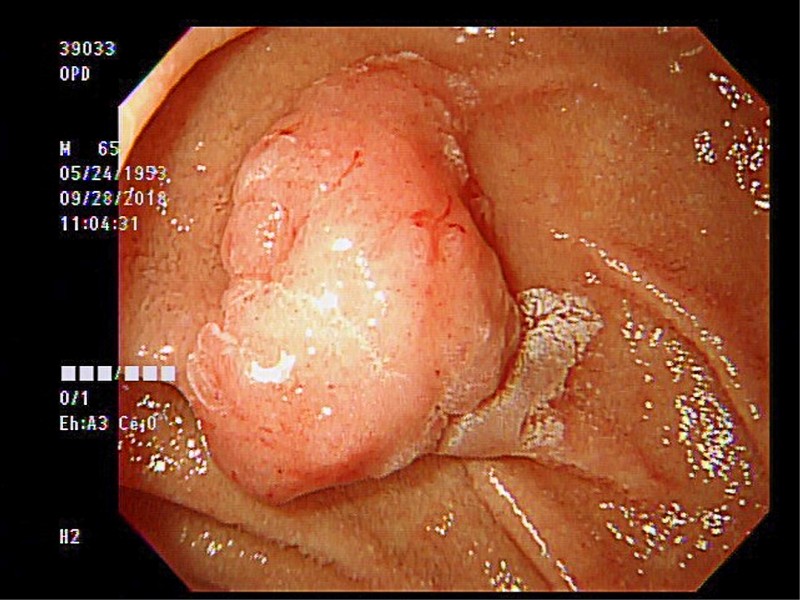

十二指腸息肉躲貓貓水中切除術除病灶 即時新聞 自由健康網